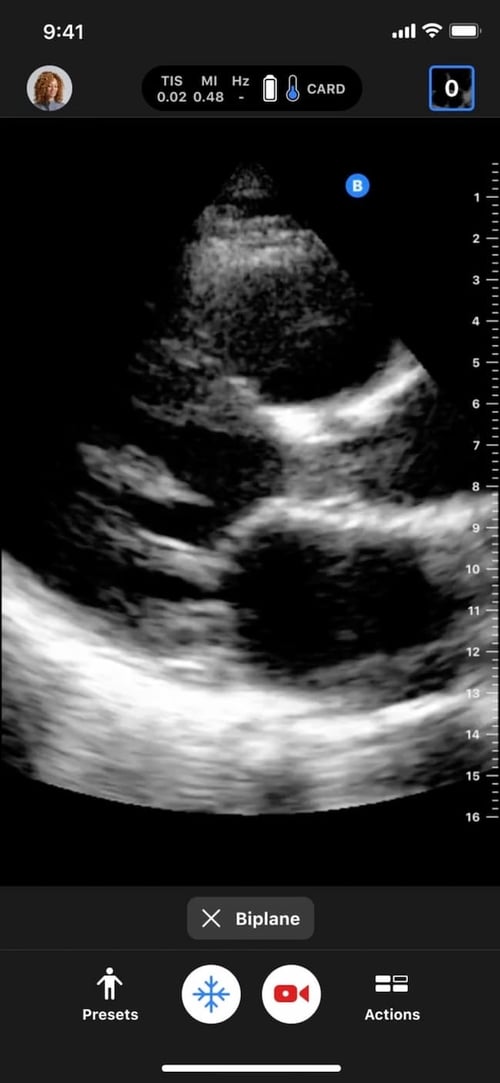

From www.butterflynetwork.com

Pointofcare ultrasound at the bedside in Cardiology Butterfly iQ+ Bedside Tte Views   we have created this online interactive module to assist with teaching and learning the assessment of cardiac function with transthoracic echocardiography. Holding subx 4 chamber view, rotate 90 degrees anticlockwise ;   transthoracic echocardiography (tte) increasing useful bedside test with increasing role in critical care;  a bedside cardiac ultrasound or echocardiogram is a quick point of care ultrasound. Bedside Tte Views.